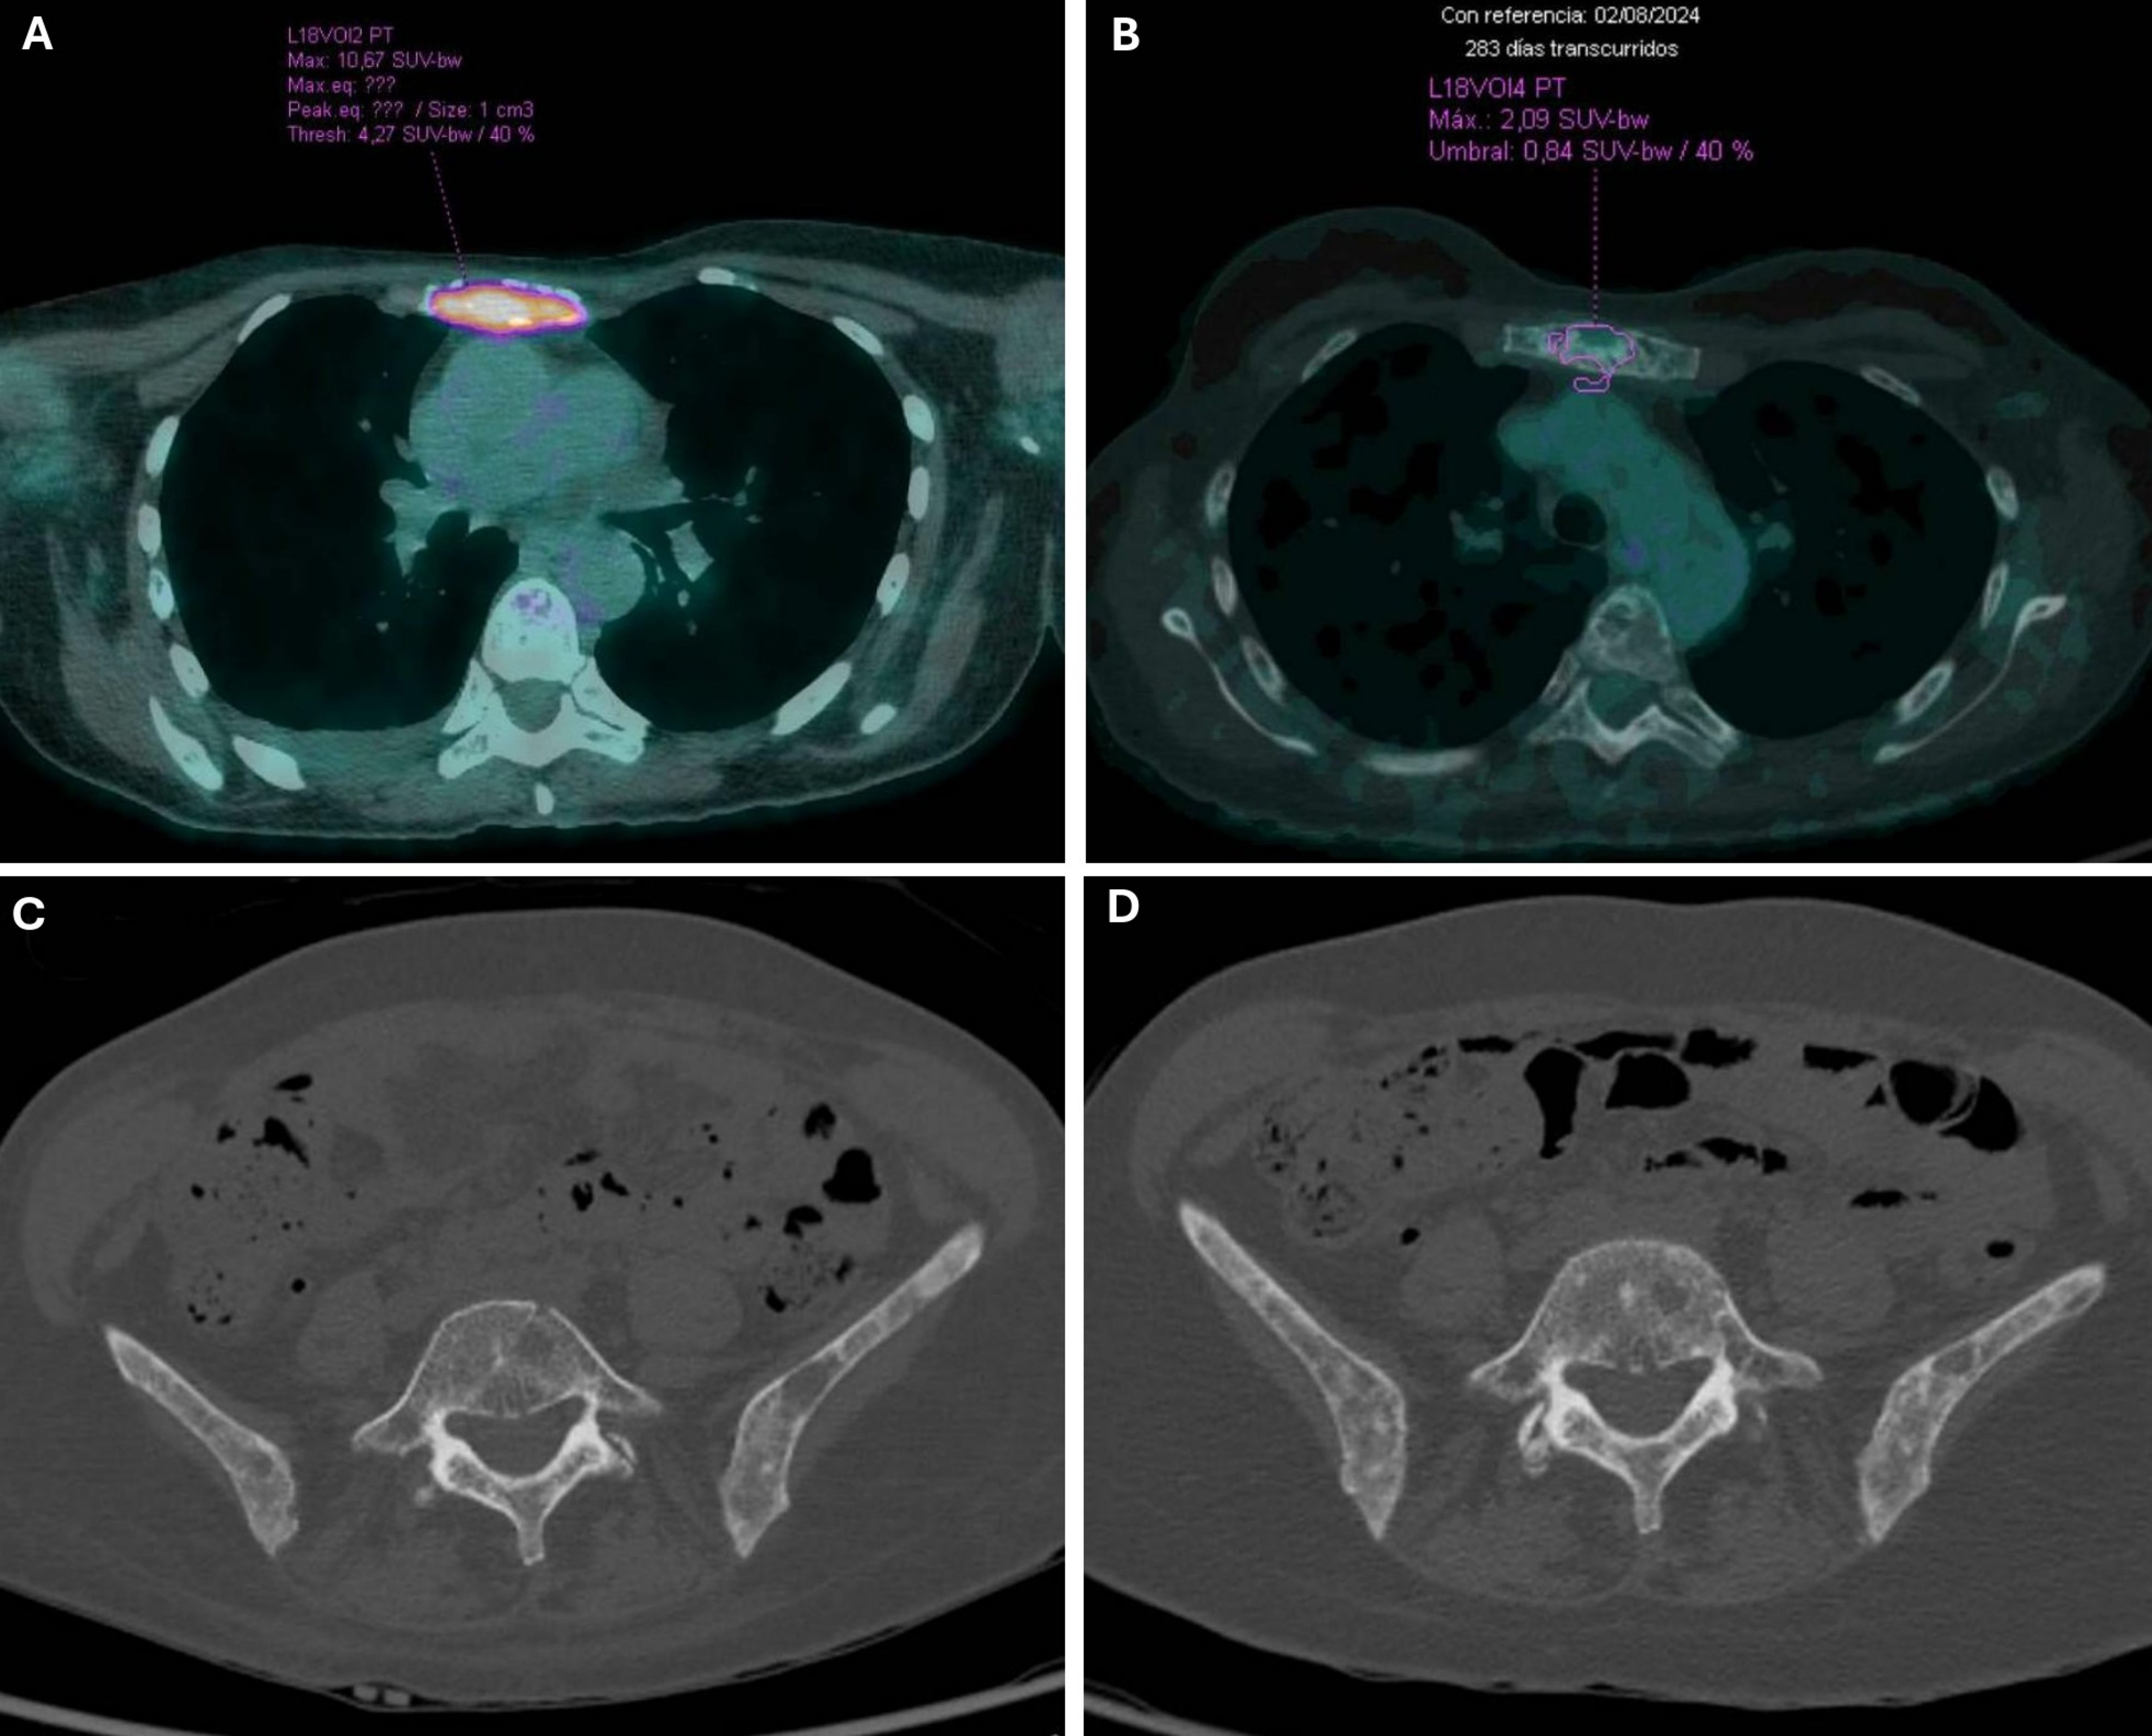

Introduction: Visceral crisis in hormone receptor-positive, HER2-negative metastatic breast cancer poses a therapeutic challenge, traditionally managed with chemotherapy due to the urgency of organ dysfunction. However, recent evidence suggests that cyclin-dependent kinase 4/6 inhibitors, in combination with endocrine therapy, may offer rapid and effective disease control even in aggressive presentations. Case Presentation: We report the case of a 52-year-old premenopausal woman diagnosed with de novo HR+, HER2-negative metastatic lobular breast cancer presenting with severe anemia and thrombocytopenia secondary to diffuse bone marrow infiltration. The patient was initially managed with letrozole and goserelin, followed by the addition of ribociclib. Clinical and hematologic parameters improved rapidly, and the patient achieved a complete metabolic response after nine treatment cycles without significant toxicity. Discussion: This case highlights bone marrow infiltration as a form of visceral crisis, reinforcing the heterogeneity of visceral crisis presentations beyond solid organ involvement. The rapid response and sustained disease control observed with CDK4/6i plus ET challenge the traditional paradigm favoring chemotherapy in such scenarios. Supporting evidence from RIGHT Choice, ABIGAIL, and recent case series further validate this therapeutic approach in carefully selected patients. Conclusion: CDK4/6 inhibitors in combination with endocrine therapy may constitute an effective and well-tolerated alternative to chemotherapy in HR+/HER2− metastatic breast cancer presenting with visceral crisis, including hematologic compromise due to bone marrow involvement. This case underscores the need to reconsider current treatment algorithms to include targeted therapies as a viable and effective option in acute and life-threatening presentations of HR+/HER2− metastatic breast cancer.